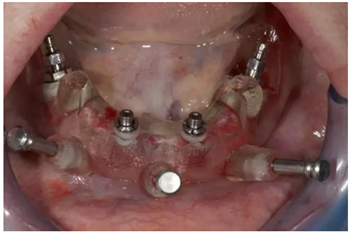

使用內(nèi)錐形連接引導(dǎo)式持釘器在下頜前牙區(qū)植入NobelReplace CC植體。

4枚NobelReplace CC植體均已植入完成:前牙區(qū)植入NP 3.5*13mm植體并裝配引導(dǎo)式基臺(tái)以固定導(dǎo)板,后牙區(qū)植入RP4.3*16mm植體并裝配內(nèi)錐形連接引導(dǎo)式持釘器。